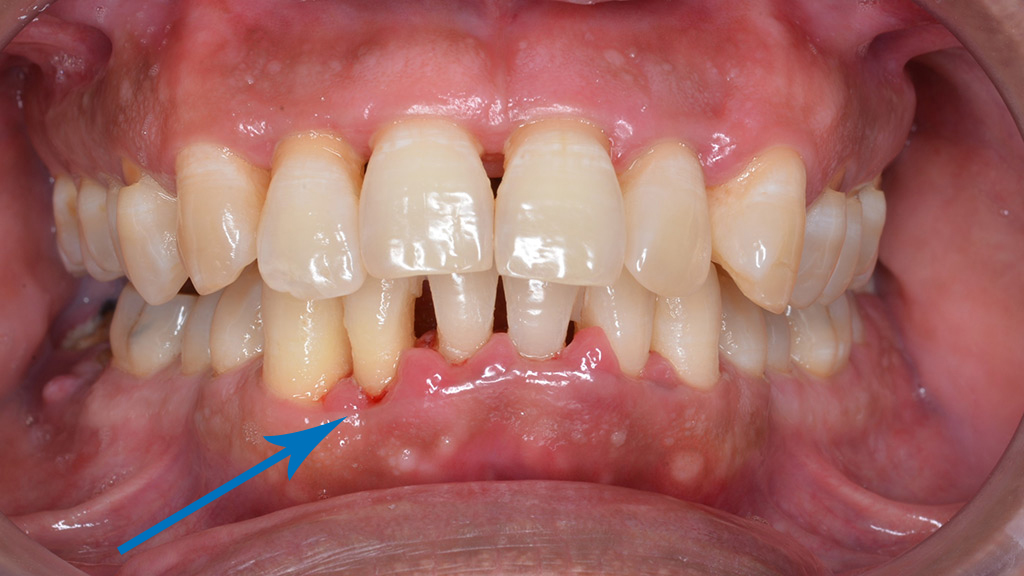

Khi ở vùng nướu lợi hoặc niêm mạc có ổ mủ (áp-xe), sẽ có chỉ định điều trị khẩn cấp.

Biểu hiện thường là sưng đỏ niêm mạc, đau nhiều hay ít, sờ thấy phập phều. Ổ mủ có thể tạm thời khỏi khi bệnh nhân tự dùng thuốc kháng sinh, chống viêm, nhưng bệnh vẫn tồn tại và đi vào trạng thái mạn tính, sau đó thỉnh thoảng bộc phát cơn cấp tính, cứ tái diễn theo chu kỳ và ngày càng trầm trọng.